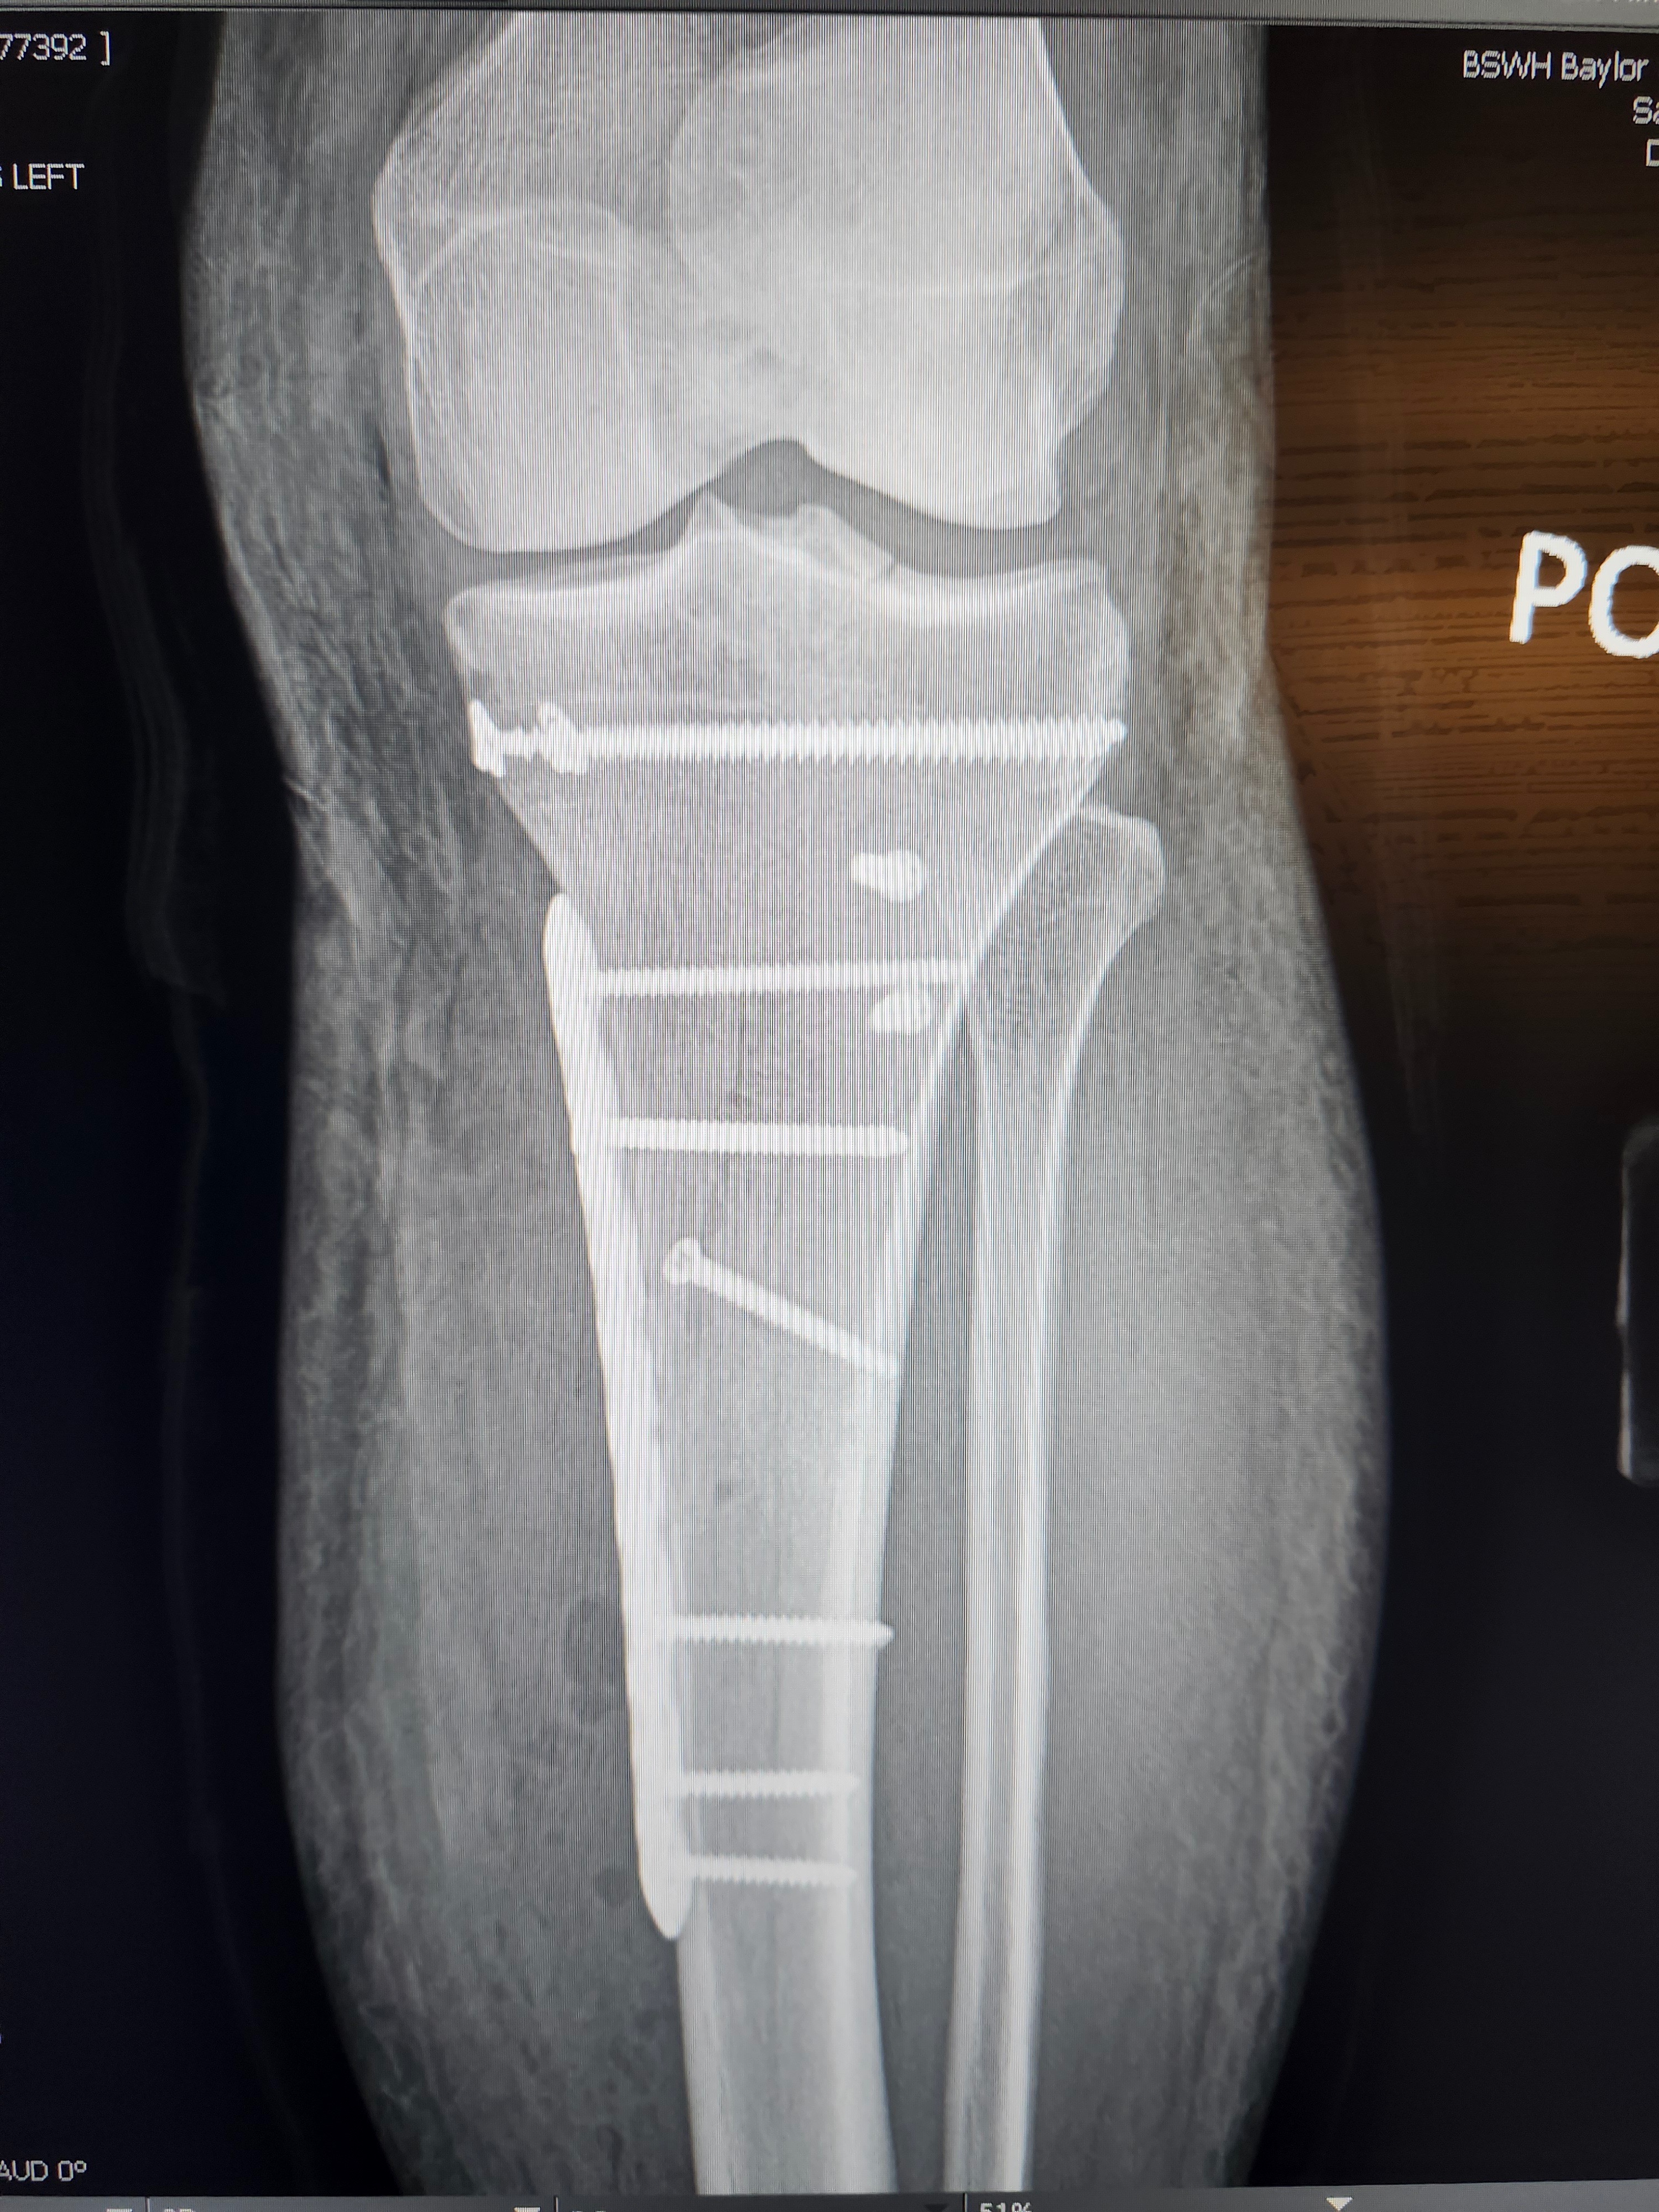

One day, Adriane was doing what she loved, teaching Kundalini yoga, helping others heal, and living her life with purpose and compassion. On February 14th, she had a devastating accident and was rushed into emergency surgery. Nothing prepares you for that phone call. Nothing prepares you to see someone you love in that much pain. She was in the hospital for 5 days before she was stable enough to come home. The surgery was successful, leaving her with a metal plate and several screws in her tibia. She now faces a long, painful recovery. She cannot stand, she cannot teach, and she cannot work. The career she built with so much love and dedication is suddenly out of reach while her body tries to heal.